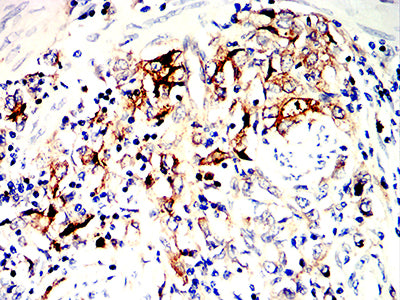

分类: 科研抗体货号: 32344别名: SS1; DRB1; HLA-DRB; HLA-DR1B应用: IHC,FCM反应种属: Human